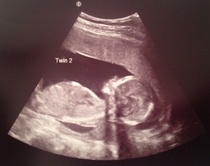

I feel like I'm bragging or something here but I just wanted to share that things went well at the hospital today and mum was able to make it after all. We even went to look for some big baggy trousers afterwards because all of a sudden I have nothing that fits my bottom half. I ended up buying 2XL pyjama bottoms with drawstrings. Beautiful soft cotton and very comfy - plain black so I am totally going to get away with dressing them up for going out!

Anyway, here are the twins at 16+1, today.

December 2014 Thread #4